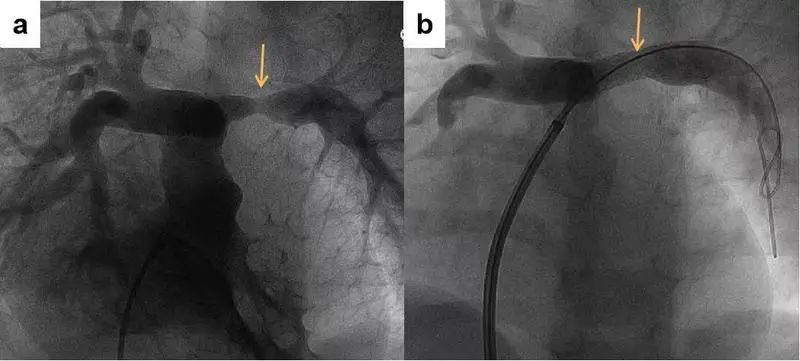

临床启动会次日,广东省人民医院张智伟教授和谢玉梅主任团队使用IBS Angel™成功完成全国首二例可吸收铁基支架肺动脉狭窄成形术。本次入组的两名患儿年龄分别为4岁和6岁,均患有复杂先天性心脏病(肺动脉闭锁),经外科矫治术后,随着年龄的增长又发现残余肺动脉狭窄。手术团队为两名患儿均植入了直径8mm、长度23mm的IBS Angel™铁基可吸收支架,顺利撑开了患儿狭窄的肺动脉。支架植入后即刻造影显示,支架位置及形态良好,肺动脉狭窄解除满意,患儿右心室压力显著降低,达到预期治疗效果。在住院观察两天后,这两名患儿均已顺利出院。

术前(a)肺动脉狭窄处在术后 (b)可见明显畅通与缓解